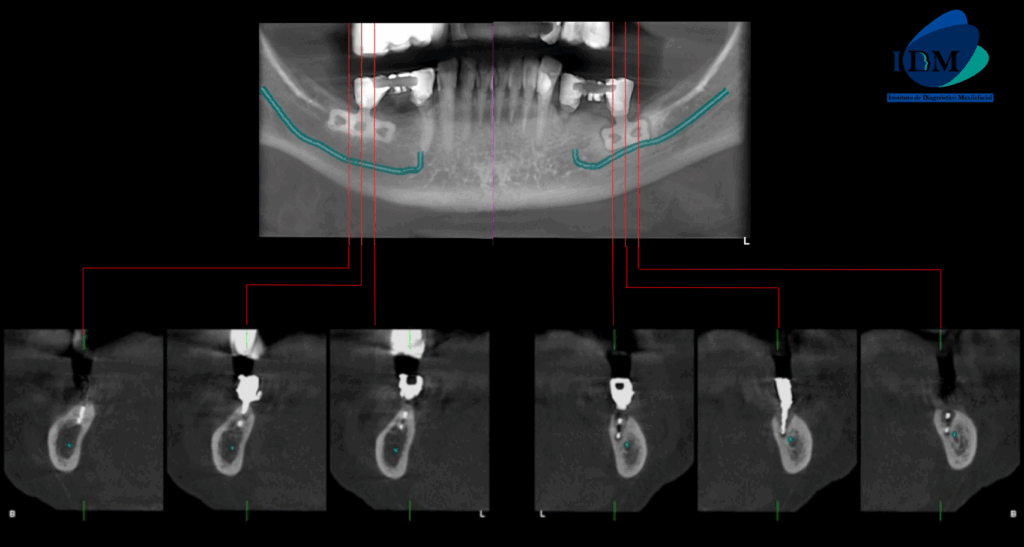

Al observar la tomografía computarizada de campo mediano se puede observar que los implantes en el maxilar inferior son efectivamente de tipo laminares o de lámina perforada, además se puede observar en vistas axiales la presencia de una imagen hipodensa circundante al implante de zona de pieza 36 (flecha azul), en vistas transaxiales y tangenciales se evidencian pérdida de continuidad de tejido óseo en tercio cervical; características que no presenta el implante en zona de pieza 46 (flecha amarilla- vista axial). Signos imagenológicos compatible con perimplantitis.

CORTES TANGENCIALES

CORTES TRANSAXIALES